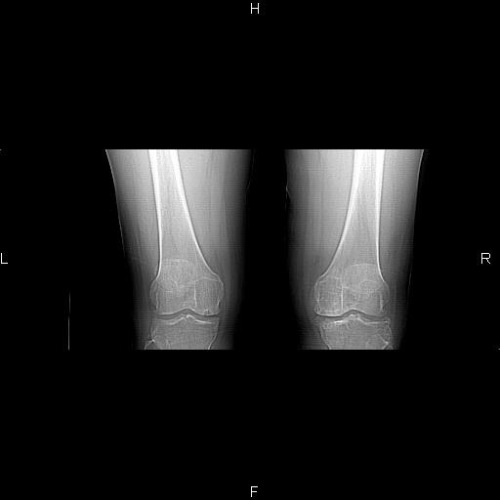

CT49618:膝关节

女 48岁,疼痛数月,加重,无明确病史

骨性关节炎

双膝关节退行性变。

膝关节退行性变。

支持双膝退变